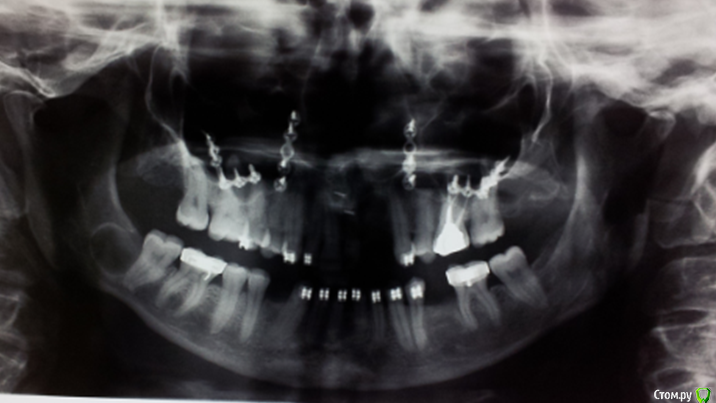

natan. Опубликовано 21 мая, 2015 Поделиться Опубликовано 21 мая, 2015 извиняюсь что прикрыл пол лица.то что надо видеть увидите.не обращайте внимания на "железяки" я не про них спрашиваю Ссылка на комментарий

Maxfac Опубликовано 21 мая, 2015 Поделиться Опубликовано 21 мая, 2015 (изменено) Дифф. диагноз?Скорее, уже результат проведенной дифдиагностики. Заключение. Думаю, что здесь врожденная расщелина губы, альвеолярного отростка и, скорее всего, неба. Изменено 21 мая, 2015 пользователем Maxfac Ссылка на комментарий

natan. Опубликовано 22 мая, 2015 Автор Поделиться Опубликовано 22 мая, 2015 (изменено) Скорее, уже результат проведенной дифдиагностики. Заключение. Думаю, что здесь врожденная расщелина губы, альвеолярного отростка и, скорее всего, неба.я наверное вас чуть запутал.да вы правильно подметили что врожденая расщелина и железяки на снимке свидетельсьвуют о том что пацент проходила операцию ортогнатическую- maxillary advancement из за недоразвития в.чел.(это было давно и не у нас в отделении).но хотел чтоб обратили внимание на basal cell carcinomas на коже лица (видно слева ,их две на этом снимке но есть еще которые не попали в кадр) и на рентгене на нижн чел.справа видна киста.т.е.у нее синдром Горлина.карциномы и кисты преследуют пациента .(ей уже давно проводилась и биопсия и генетическая проверка с подтверждениес синдрома). Изменено 22 мая, 2015 пользователем natan. 2 Ссылка на комментарий

ПалСаныч Опубликовано 22 мая, 2015 Поделиться Опубликовано 22 мая, 2015 (изменено) Я вам могу привести как минимум три диагноза, на что похожи опухоли на коже. И каким образом нам стоило догадаться что это базалиома? А киста могла остаться от удаленной восьмерки? Для проведения дифдиагноза двух фотографий маловато.... Изменено 22 мая, 2015 пользователем ПалСаныч 3 Ссылка на комментарий